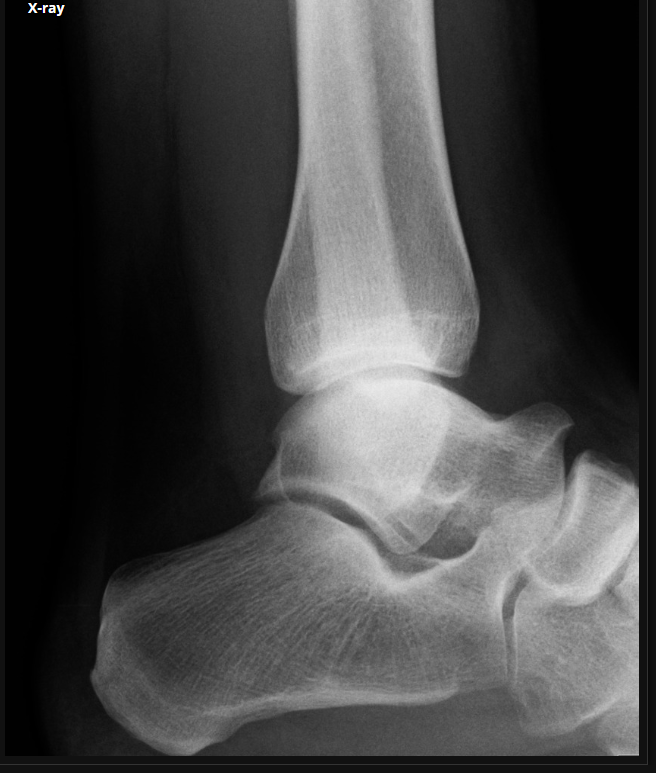

Trauma

Fratura do platô tibial lateral - Schatzker tipo 2 (traço de fratura + depressão do plato lateral).